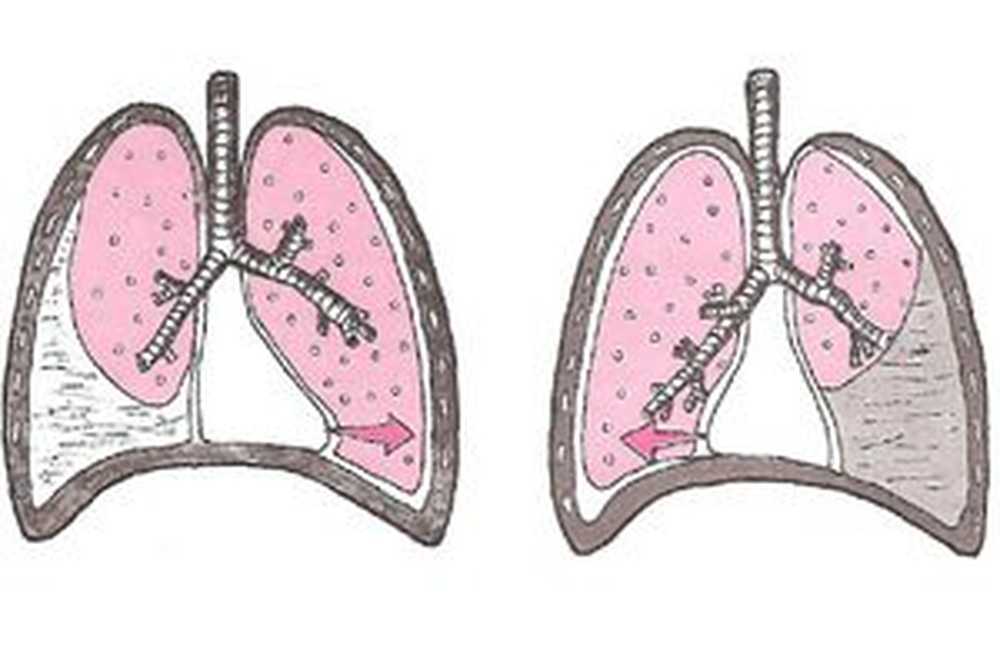

Симптомы и причины скопления воды в легких

Раздел: Ракурсы просвещения